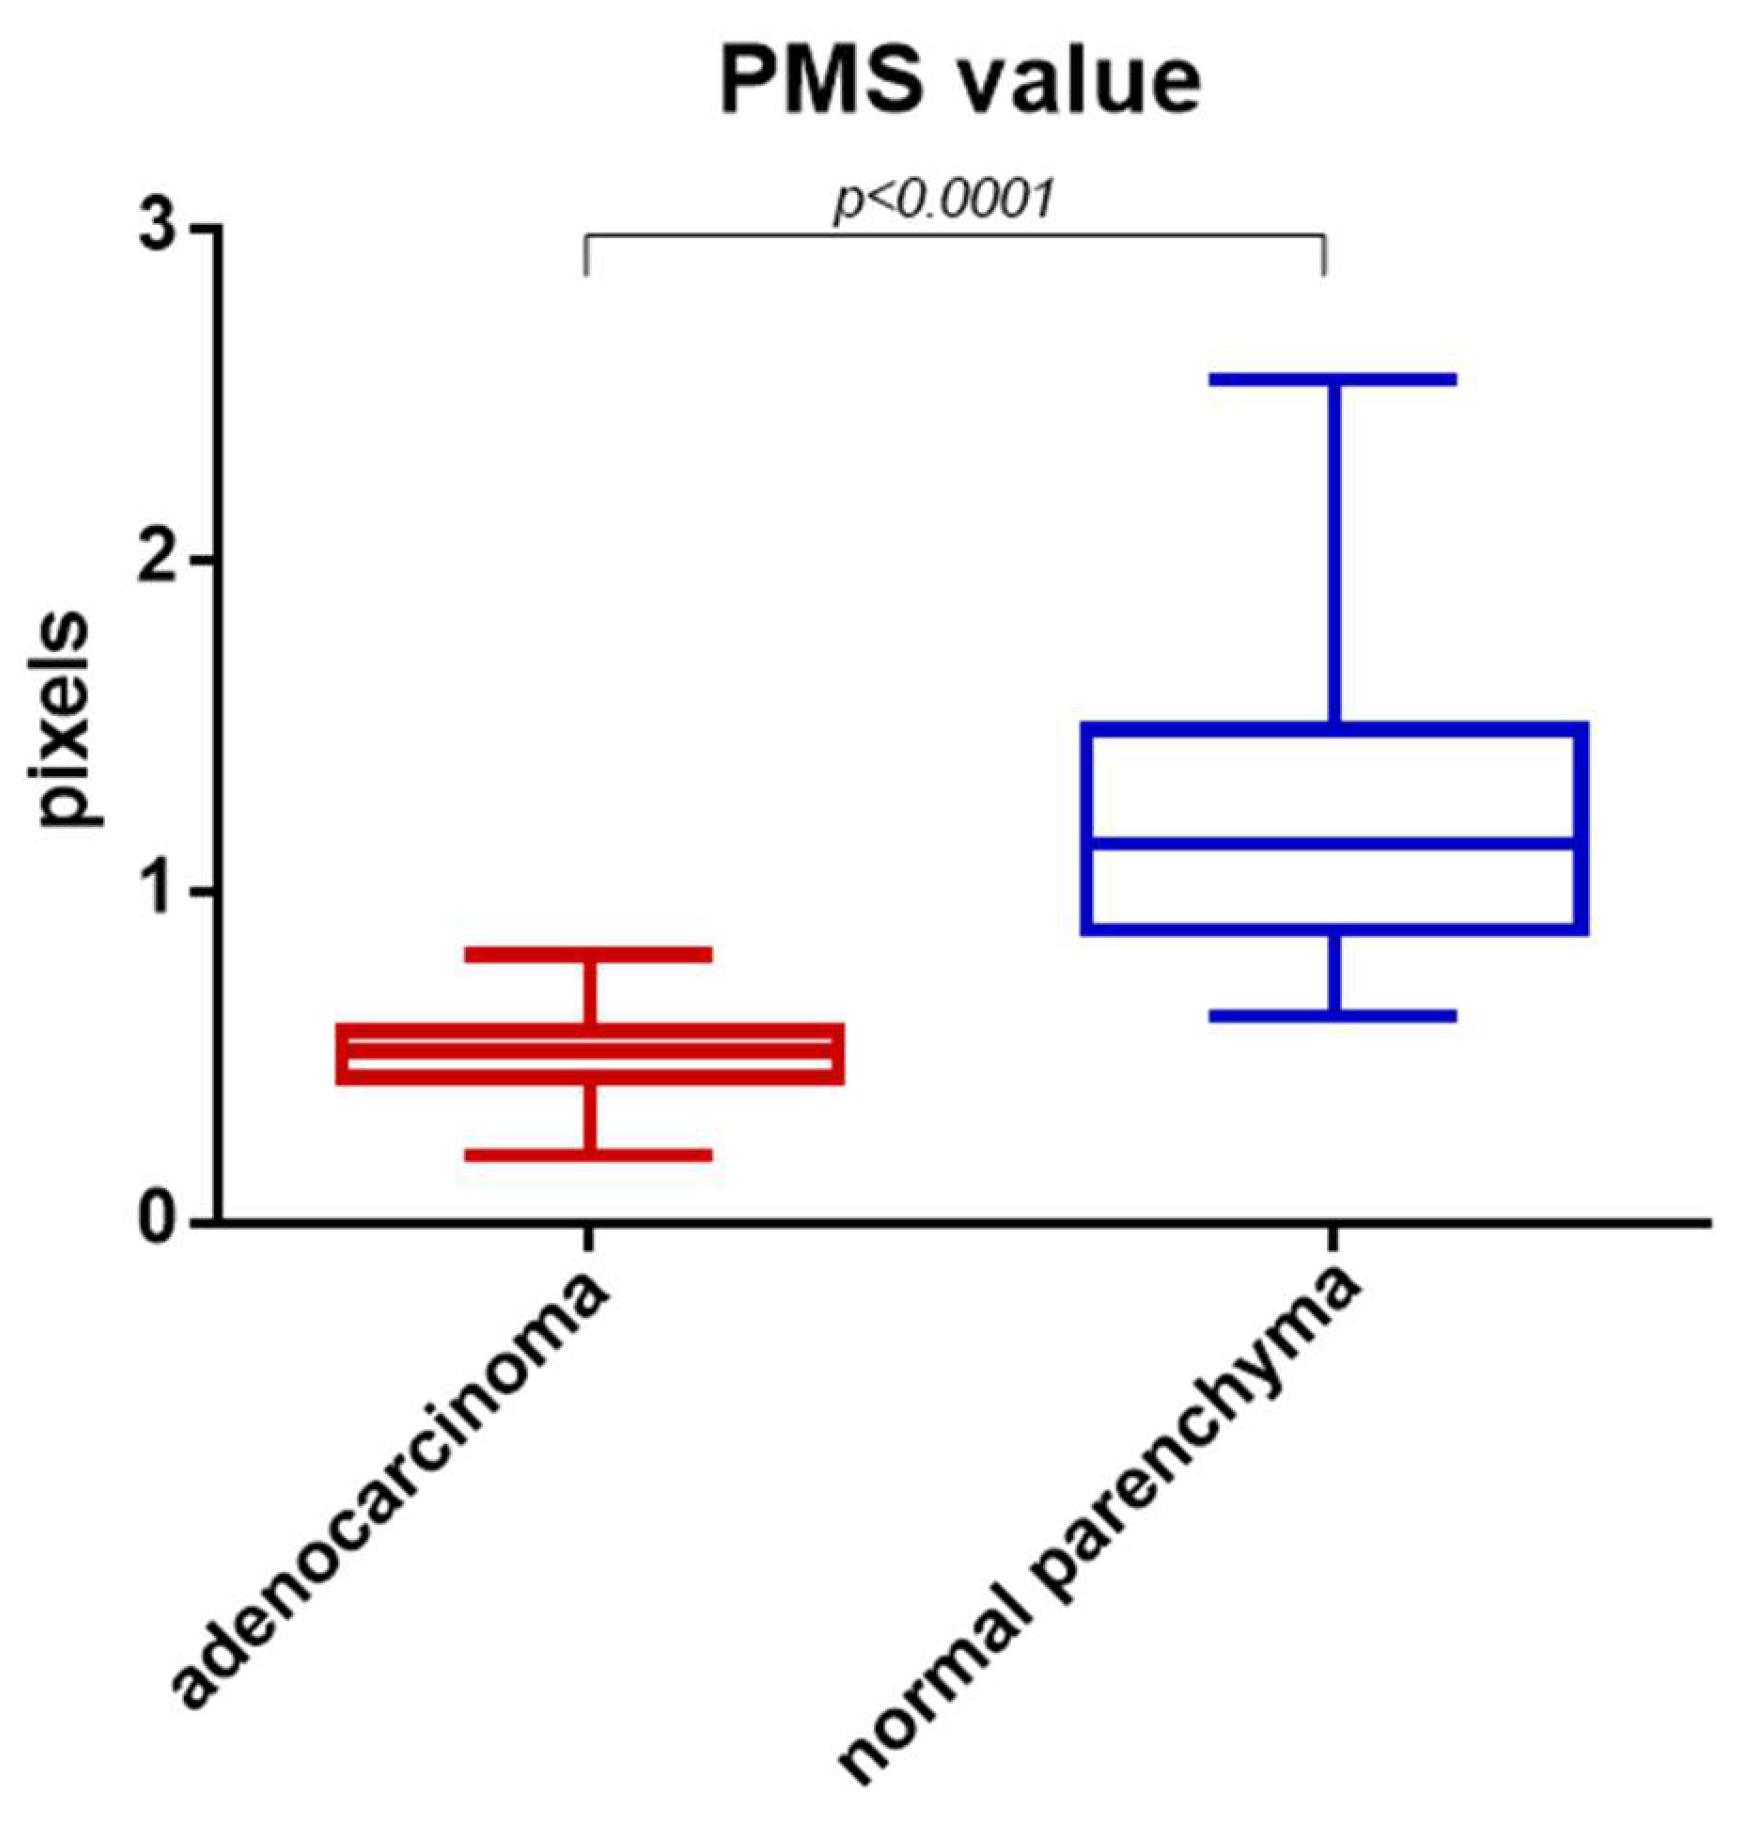

3. Results